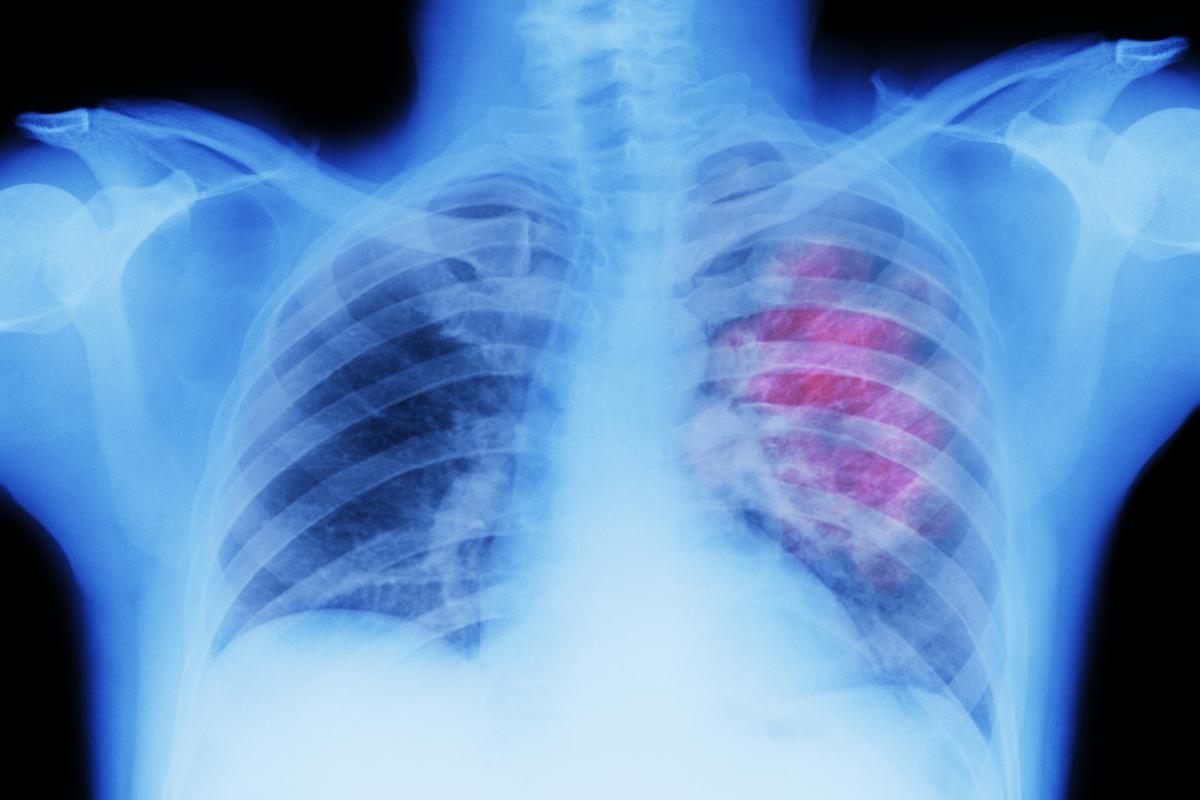

Una investigación liderada por el Cancer Center Clínica Universidad de Navarra y la compañía alemana Catalym ha demostrado clínicamente que la neutralización de la proteína GDF-15 potencia el tratamiento con inmunoterapia frente al cáncer, al menos en una fracción de los pacientes cuyos tumores se habían hecho resistentes a los tratamientos convencionales.

Los resultados, publicados en la revista Nature, muestran que, cuando se bloquea GDF-15, las células del sistema inmunitario que son capaces de reconocer y destruir tumores superan el obstáculo y lo atacan eficientemente hasta conseguir que reduzca su tamaño o incluso desaparezca.

El ensayo clínico en fase I-II se ha desarrollado también en hospitales de Madrid y de Barcelona —destacando la participación del VHIO (Vall d'Hebron Instituto de Oncología) y de START Madrid CIOCC (Centro Integral Oncológico Clara Campal)— y ha probado el tratamiento en aproximadamente 200 pacientes con tumores sólidos que habían mostrado resistencia al tratamiento con anticuerpos anti-PD-(L)1.

En este ensayo, las personas participantes recibieron dosis escalonadas de un anticuerpo monoclonal desarrollado por Catalym que neutraliza GDF-15 en combinación con otro fármaco que neutraliza PD-1. Posteriormente, se obtuvieron biopsias tumorales en diferentes momentos para analizar el cambio de comportamiento de las células del sistema inmunitario durante el tratamiento.

El estudio ha demostrado que la combinación de ambos fármacos induce respuestas antitumorales con excelente tolerabilidad y, además, los análisis de laboratorio ponen claramente de manifiesto el mecanismo de acción.

“Hemos observado reducciones objetivas de la carga tumoral que son profundas y duraderas en una fracción de los pacientes tratados, así como algunas respuestas completas con desaparición de todas las lesiones tumorales medibles en pacientes que no habían respondido previamente a múltiples tratamientos”, ha subrayado Melero.